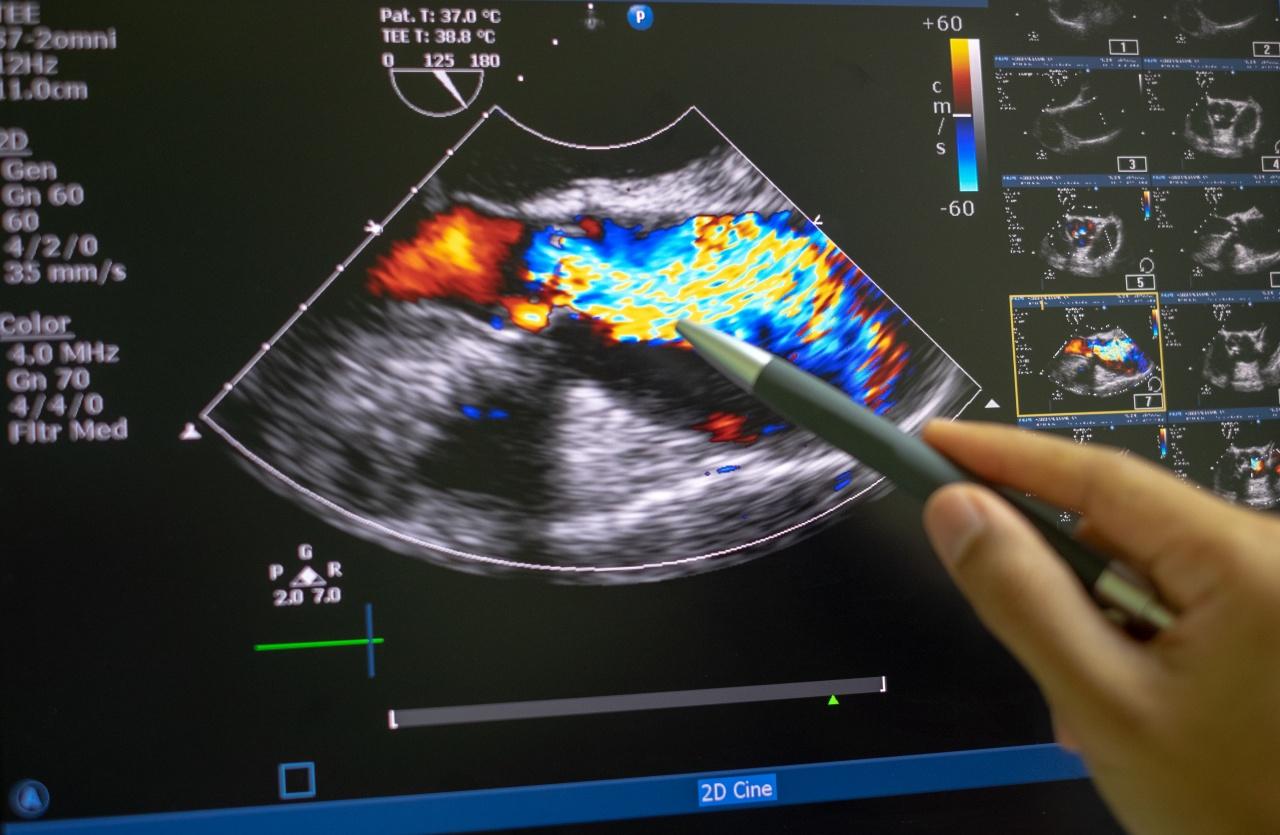

• โรคลิ้นหัวใจ (Heart valve disease)